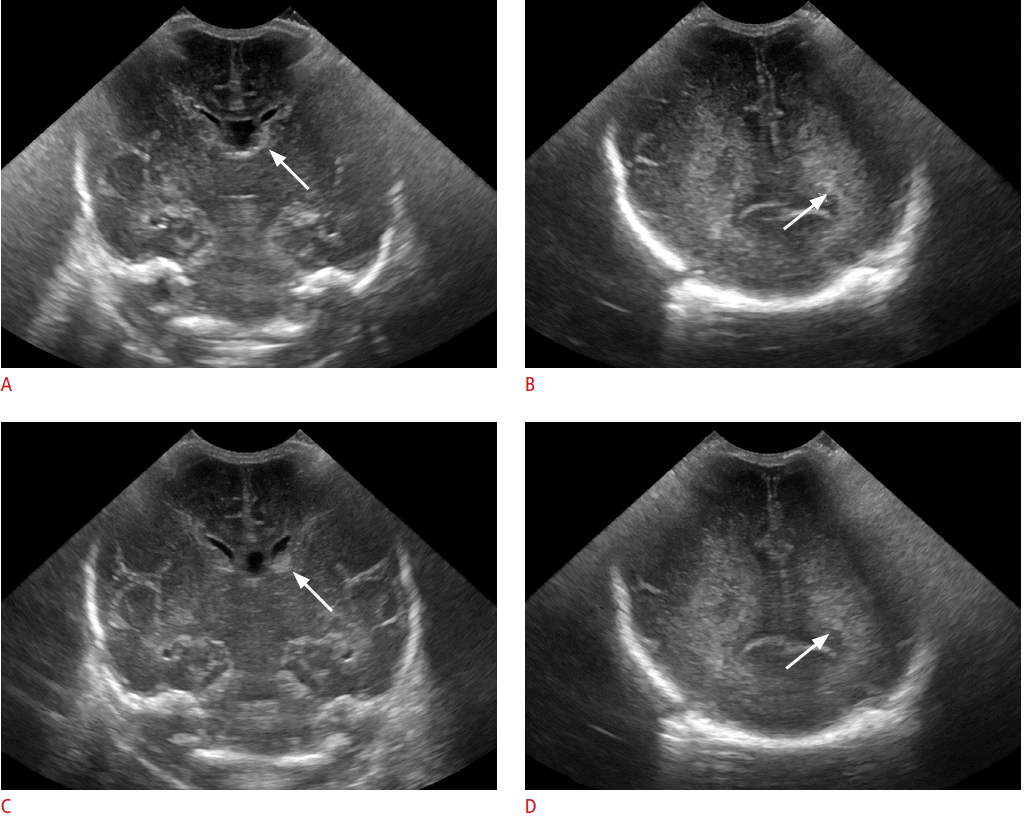

Trong quá trình kiểm tra, một máy siêu âm sẽ phát ra sóng siêu âm vào đầu và hình ảnh được ghi lại trên máy tính. Các hình ảnh đen trắng cho thấy cấu trúc bên trong của não, bao gồm cả nhu mô não, não thất và các mạch máu.

Các bác sĩ đặt siêu âm thóp khi có mối quan tâm về các vấn đề thần kinh ở trẻ sơ sinh. Trẻ sinh non cần được chăm sóc đặc biệt thường xuyên phải siêu âm đầu để loại trừ các biến chứng thần kinh của sinh non, chẳng hạn như xuất huyết não hoặc tổn thương chất trắng quanh não thất do ngạt.

- Chảy máu trong mô não hoặc trong não thất

- Não úng thủy

- Một khối trong não, chẳng hạn như khối u hoặc u nang

- Nghi ngờ biến chứng viêm màng não